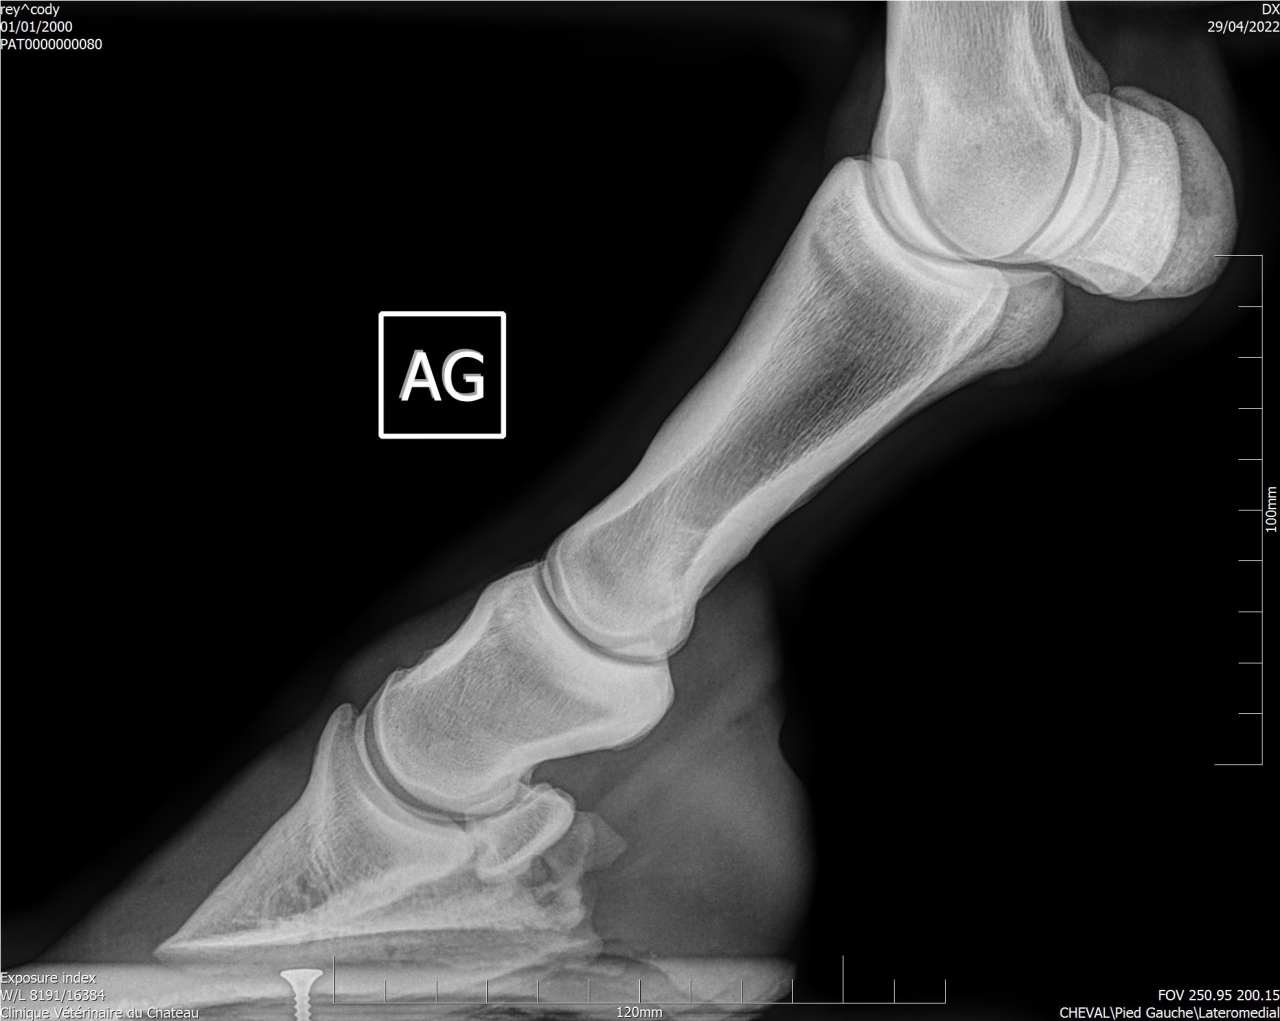

| Dire merci | Suite aux radios faites sur Cody, j'ai fait passer un véto spécialisé en boiteries. Examen : AG paturon légèrement déformé (je n’avais jamais remarqué) Pince + Fers avec oignons et plaques Planche négative (apparemment Cody a bien réagi) Flexions statiques normales Légère irrégularité ADT à main dte (effectivement pas trop mal, ça a été pire) Radiographies fournies : Légère ossification processus palmaires (moi je ne vois rien de particulier sur les radios) Légère arthrose interphalangienne proximale (idem) 1 à 3 fossettes sur chaque naviculaire (apparemment pas catastrophique, le véto m’a montré d’autres radios de chevaux naviculaires pour comparer) Recommandations : Marechalerie : poursuivre à l’identique (Oignons et plaques) Traitement : Dextropine et Navitol Voici les radios : ![]() ![]() ![]() ![]() Si quelqu'un pouvait m’expliquer en termes simples ![]() |

| Dire merci | Je suis pas experte en lecture de radios, loin de là, mais le bord distal du naviculaire semble quand même largement plus vilain que les cartilages palmaires ? Et ça sur les deux pieds.Je serai par contre curieuse de voir des photos du parage vu ce qu’on voit aux radios.. Message édité le 01/07/22 à 22:45 |

| Dire merci | La où il y a les fossettes. En gros la partie en rapport avec le tendon du fléchisseur profond. Mais il a l’air d’être super long au moment des radios? |

| Dire merci | Honnêtement j'ai vu bien pire en ossification des processus palmaires, il faut que je retrouve les radios. Pour le reste je rejoins les autres les pieds sont beaucoup beaucoup trop longs. |

| Dire merci | Je pense qu’un cheval sur deux aura les cartilages plus calcifiés que celui là Peut être même plus… Son plus gros soucis sur les radios c’est quand même l’entretien des pieds. Et c’est le seul facteur sur lequel on peut jouer et qui n’est pas irréversible Faire un parage coûte moins cher que 2 paires de radios |